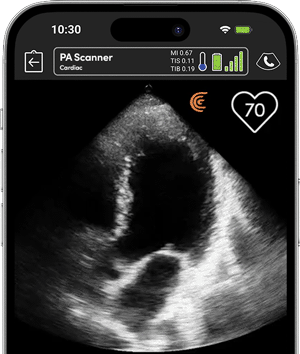

• Realizar una ecocardiografía dirigida por objetivos al lado de la cama

• Supervisar los cambios del paciente durante un paro cardíaco

Real-time heart rate display without ECG for rapid, critical assessment.

Cardiac Calculations

Comprehensive package for precise cardiac function assessment.